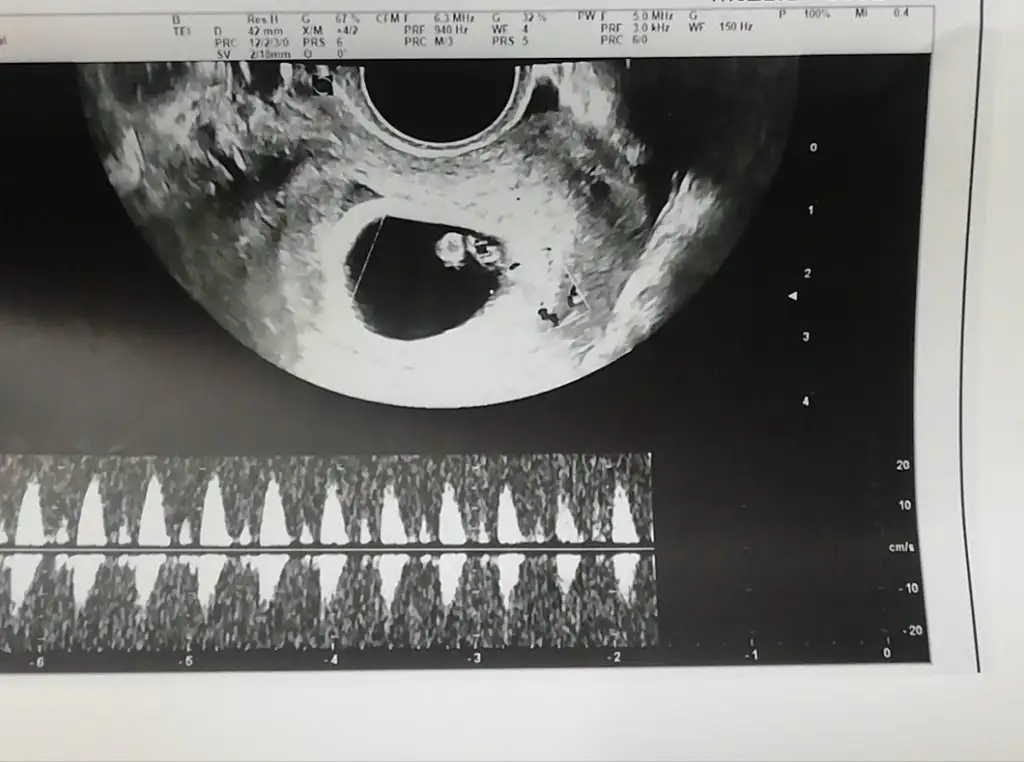

Yorum yapar mısınız 5+5 ama 6 düşünebiliriz dedi doktor